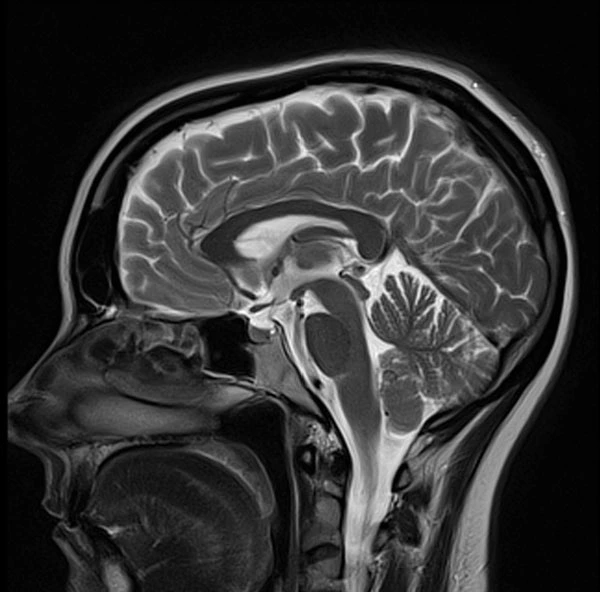

제이 : 방사선사는 일반적으로는 X-Ray 촬영을 하는 사람으로 알려져 있는데 ‘영상의학’을 전반적으로 아우르는 테크니션이라고 할 수 있어. X-Ray를 시작해서 경력이 쌓이면서 수술실에서 C-Arm 엑스레이, CT 스캔 MRI, 초음파 등의 검사를 진행하고 병변이 보이는 응급한 경우 의사에게 바로 리포트를 해서 조치를 취하게 해. 호주에서 2009년 영상의학 학사학위 유학을 시작하며 이 일에 연을 맺었어. 실무 경력은 한국에서 방사선 촬영병으로 2년, 호주의 요양병원에서 CARE NERSE로 4년, 그리고 졸업 후 방사선사로 1년 차로 총 7년 째 의료계에 종사하고 있어.

제이 : 그냥 무조건적으로 호주가 착한 나라라서 더 존중해주는 것은 아니야. 내가 봤을 때는 물리치료사나 방사선, 안경광학 등의 교육과정이 한국에 비해서 더 심화되어 있어서 그래. 영상의학을 예를 들면 한국의 방사선과 과정에 비교해서 훨씬 심화된 교육을 받아. 해부학도 엄청 빡세게 공부하고 영상을 찍는 것을 넘어서 다 판독할 줄 알아야 하거든. 혈관 하나하나, 근육 하나하나, 모든 인대들의 이름도 다 알아야 해. 의사 한 명이 독단적인 진단을 내리기 전 방사선사가 한번 더 판독을 함으로써 오류를 줄이고 환자의 생존율을 높이기 위함인 거야. 그런데 한국에서는 내가 방사선사라고 하니까 그냥 엑스레이 사진 찍는 아저씨구나, 하더라고. 방사선 공부한다고 하니까 왜 그런 거 하냐고 하는 사람도 있어서 이 일 한다고 말하기 싫을 때도 있었어. 방사능이랑 헷갈리다 보니 위험하고 험한 직업이라고 생각하기도 하고.